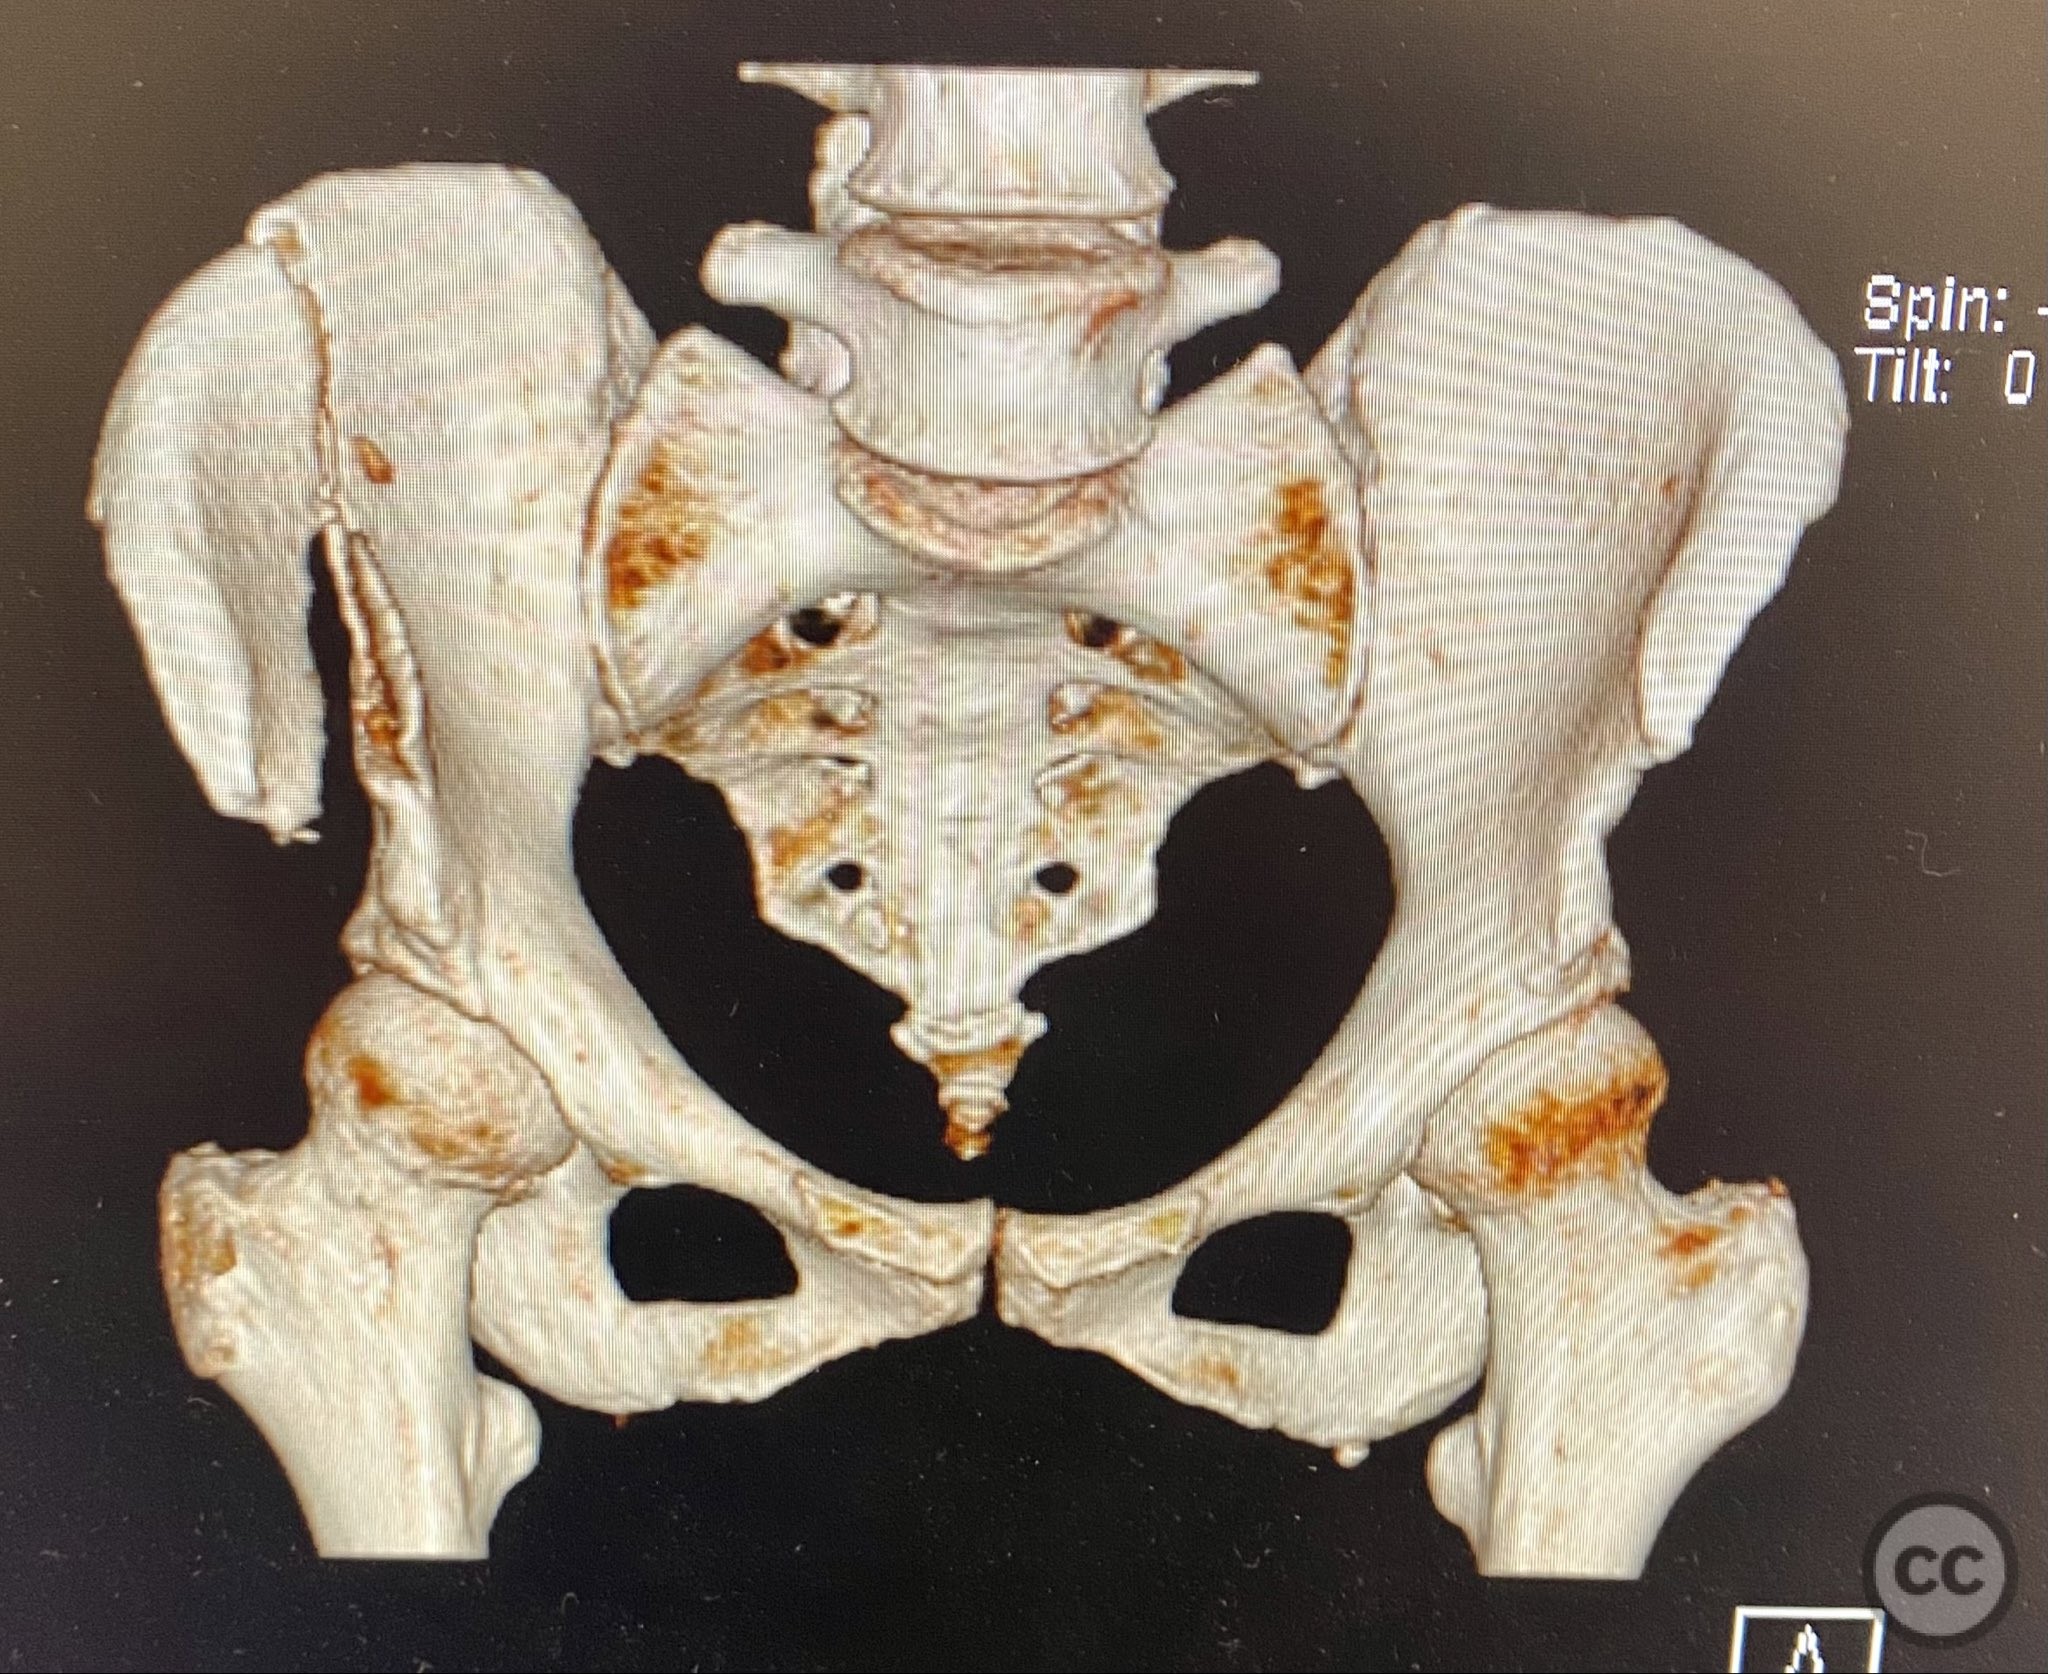

Clinical Details

Clinical and radiological findings:  A middle-aged patient sustained a closed, displaced, and comminuted fracture of the right os ilium following a fall from height. Initial AP pelvic radiograph and 3D surface rendered imaging demonstrated significant comminution, displacement, and poor bone quality. The patient was unable to mobilize due to pain. No associated neurovascular deficit or additional pelvic ring injury was reported. AO/OTA classification: 61B2.2 (partial articular, comminuted iliac wing fracture).